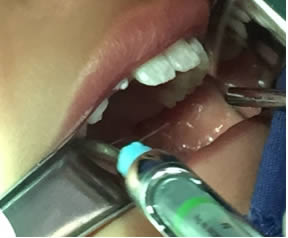

• Se realizó una incisión horizontal en la parte media del frenillo con hoja de bisturí No. 15 y mango No. 3, posteriormente se comenzó a cortar el frenillo de arriba abajo cuidando la anatomía de la región y la zona de las carúnculas sublinguales de los conductos de Wharton y Rivini. (Figuras 5 y 6).

Figuras 5 y 6. Incisión y corte del frenillo.